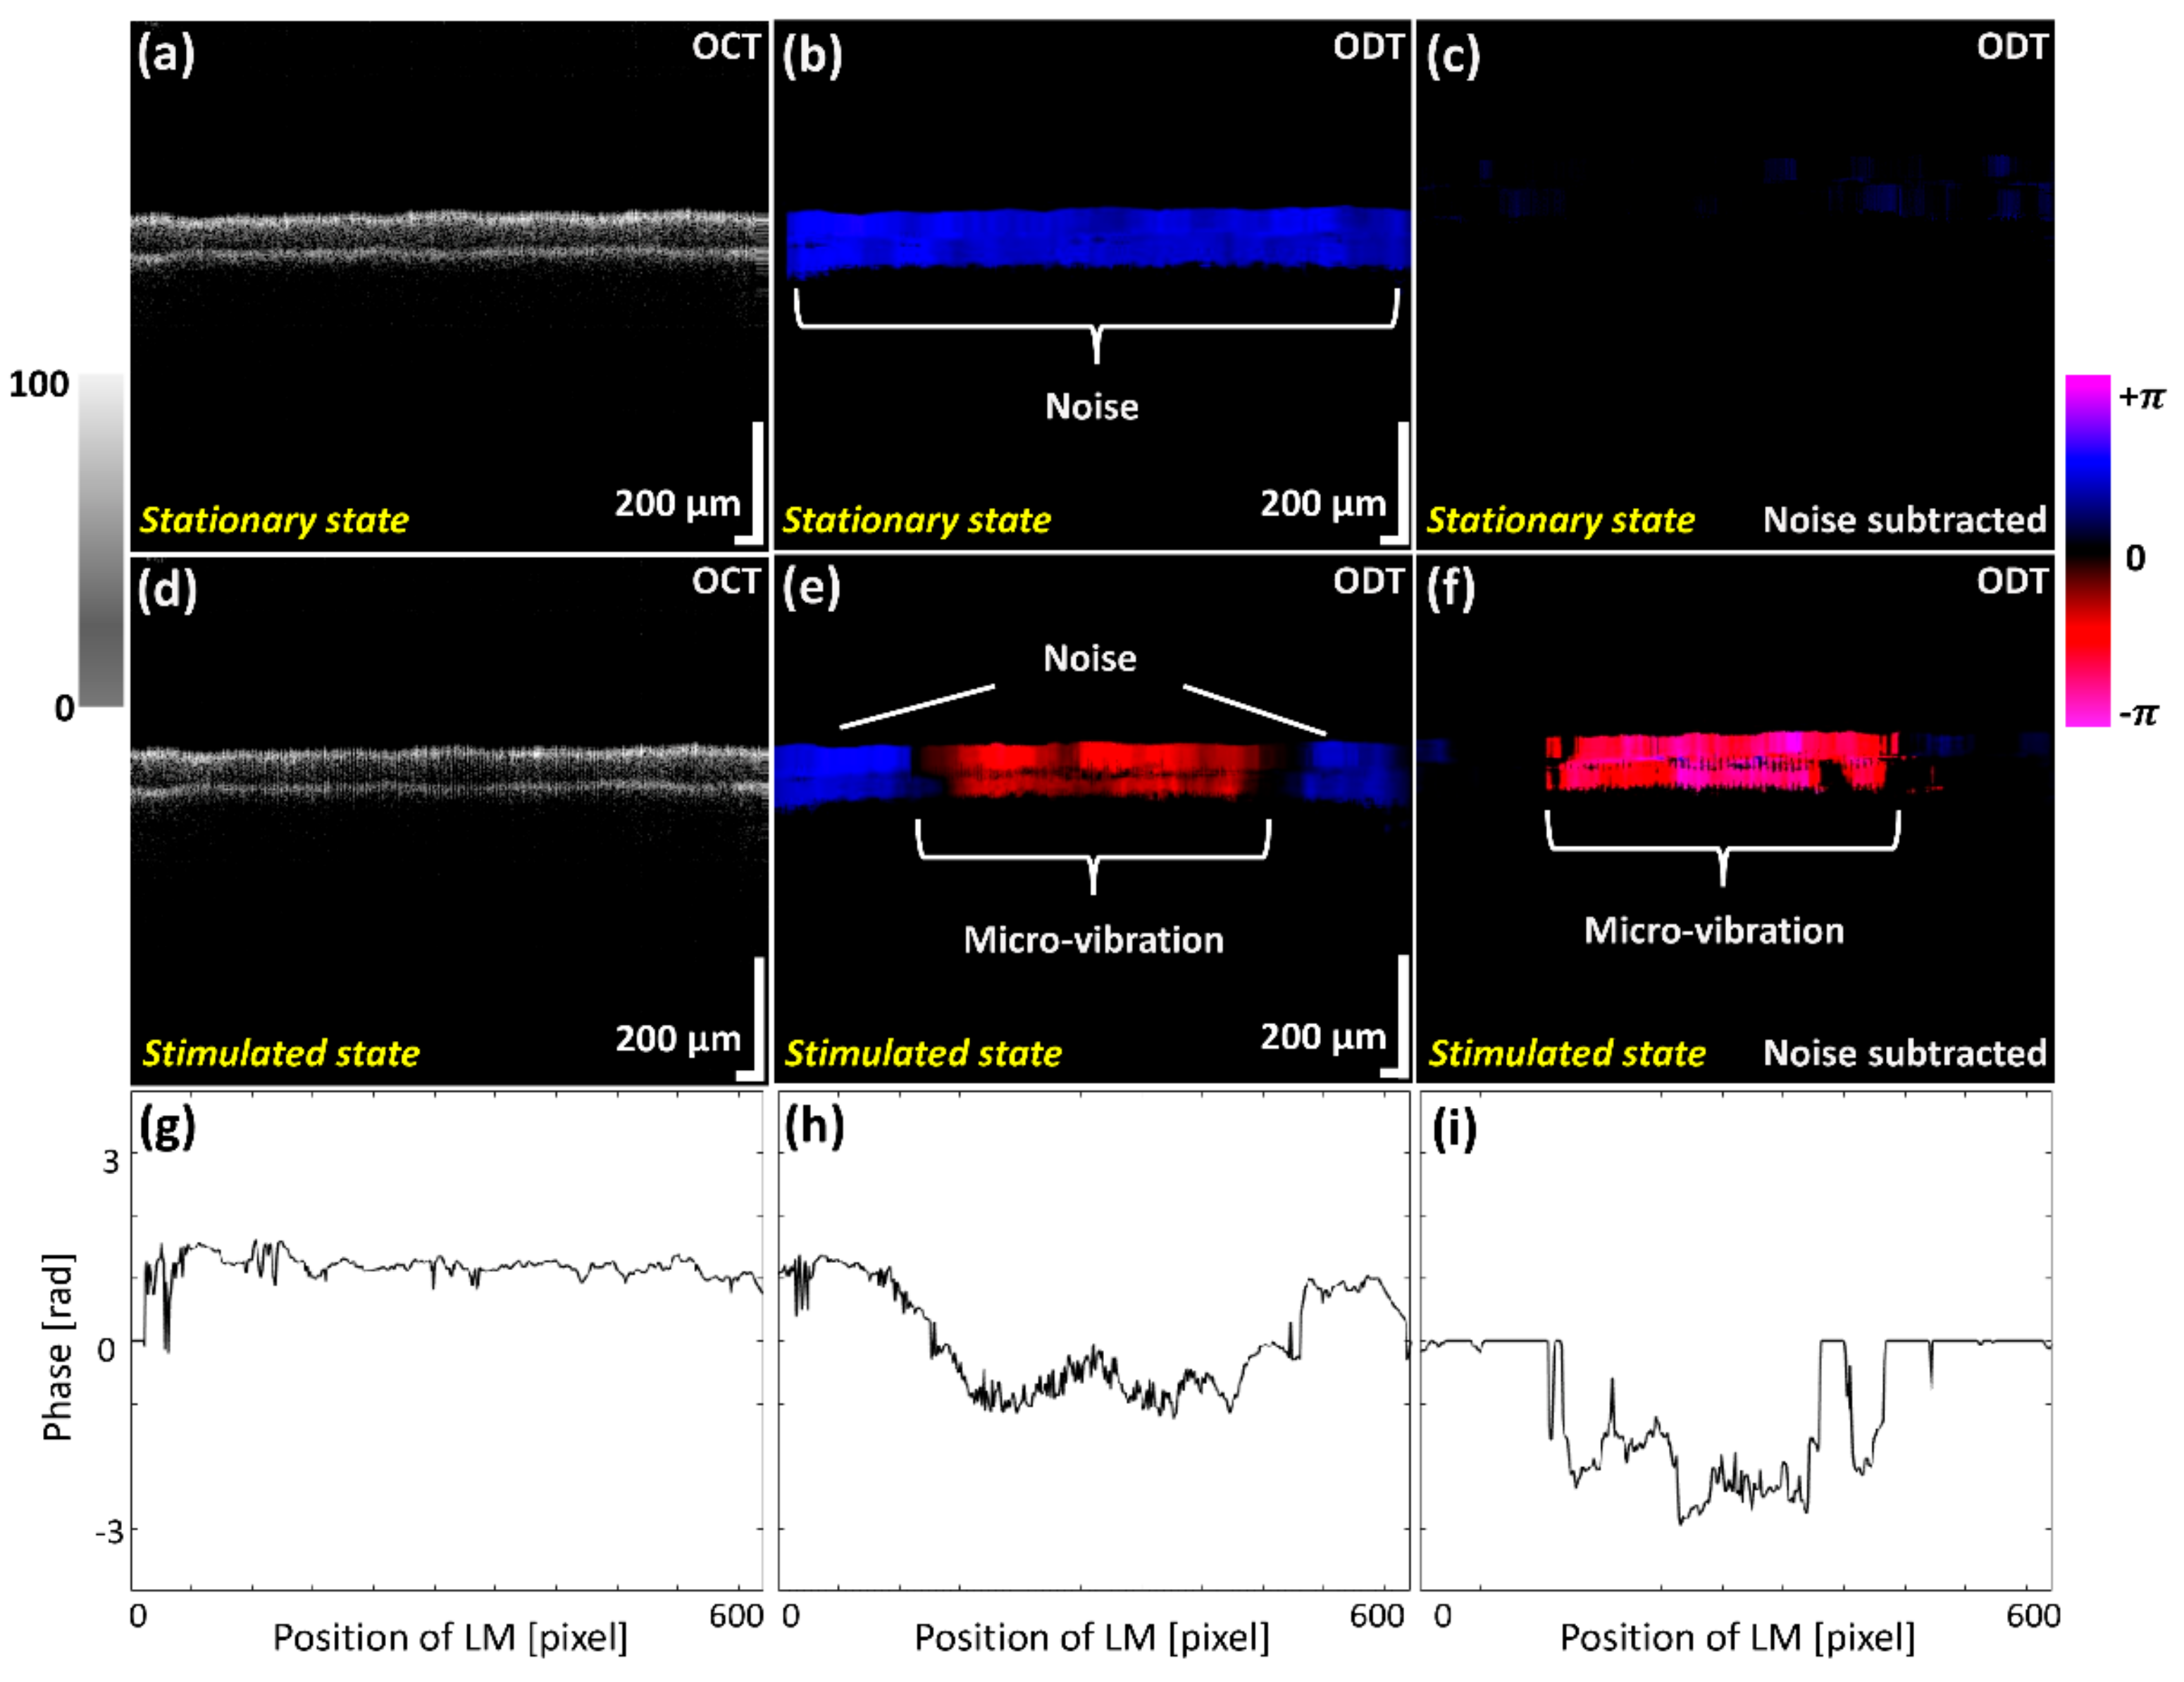

3.2. OCT and ODT Cross-Sectional Assessments for Micro-Vibrations

The micro-vibrations were investigated using OCT and ODT cross-sectional images while scanning the membrane before and after exposing to the diverse frequency ranges. Figure 4 shows the OCT and ODT results of the two different states before applying sound indicated as a stationary state, and after applying sound expressed as a stimulated state. The illustrated OCT and ODT results of Figure 4a,b were obtained during the absence of sound waves (control), where Figure 4d,e represent oscillation images of the latex membrane, which were acquired while providing a 2 kHz sound wave frequency. Although vibration effects can be slightly recognized in the grayscale OCT image of Figure 4d, identification of prominent fine oscillations is difficult to distinguish. Slightly occurred phase shift evaluations caused by micro-vibrations with external noise effect were color mapped in ODT results, as shown in Figure 4b,e.

In order to eliminate the aforementioned noise effect, we used the phase subtraction method, comparing the phase difference before and after applying sound. The results of Figure 4c,f demonstrate the ODT images with the applied noise filtering software to minimize the unnecessary noise effect of Figure 4b,e. Although erroneous numerical values have been significantly reduced comparatively, slight noise signals were still left and unable to be removed in the (+) direction due to the sensitivity of measuring micro-vibrations and the inconsistency of phase shift generated by scanners. To quantitatively validate the effect of the phase subtraction method on the ODT image, the phase data of Figure 4b, e and f were plotted in Figure 4g–i. Figure 4g shows the initial noise generated from the external aforementioned factors. In addition, the result of removing a redundant noise, which is shown in Figure 4g, was verified by comparing with Figure 4h,i. After subtracting the noise, the pure fine vibration of the latex membrane was measured in this study. These results revealed that the noise removal was sufficiently accomplished to verify the micro-vibration of whole latex membrane.

Figure 4. Two dimensional optical coherence tomography (2D-OCT) and Optical Doppler tomography (ODT) images acquired before and after exposing the latex membrane to the sound waves. (a) 2D-OCT image of latex membrane before applying sound. (d) 2D-OCT image of vibrating latex membrane. After Doppler image processing, (b,e) are 2D-ODT images with severe noise. (c,f) are processed 2D-ODT images with an algorithm to subtract phase differences before and after sound is applied, eliminating unnecessary noise at (b,e). (gi) are indicated the phase data of (b), (e) and (f), respectively.